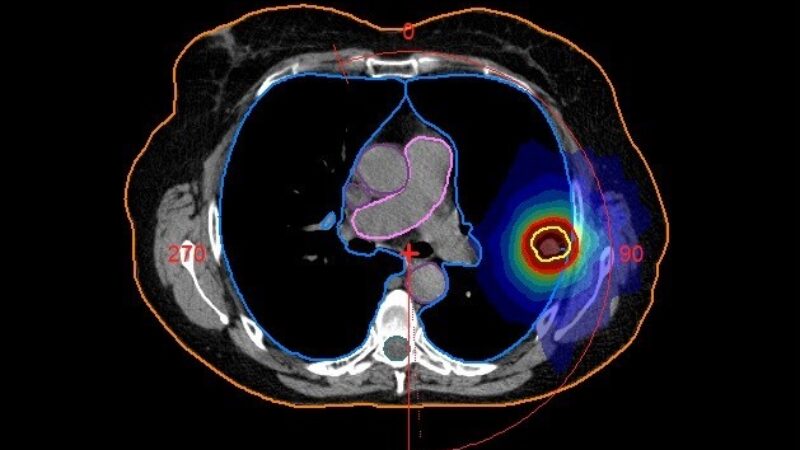

Then, specialists called medical physicists and dosimetrists work together to figure out the best way to deliver the right amount of radiation. The goal is to hit the cancer with the strongest dose while keeping the nearby healthy areas safe. This careful planning helps make your treatment both effective and safe.

Before your radiotherapy begins, your cancer treatment team, which includes doctors, radiation therapists, and medical physicists, work together to design a treatment plan tailored specifically for you. The dosimetry team is responsible for the technical side of this process, making sure the right amount of radiation (called the “dose”) is used.

The radiotherapy physics team consists of highly trained medical physicists and technical staff who specialise in understanding how radiation works and how to deliver it safely. Their primary job is to ensure that all the machines, software, and equipment used in your radiotherapy are working correctly and that the radiation dose you receive is exactly what’s needed for your treatment.

The physics department ensures that every aspect of your radiotherapy is scientifically sound and safe. By maintaining and monitoring the complex technology used in your treatment, they help deliver precise radiation doses that are essential for effectively treating cancer while minimising side effects.